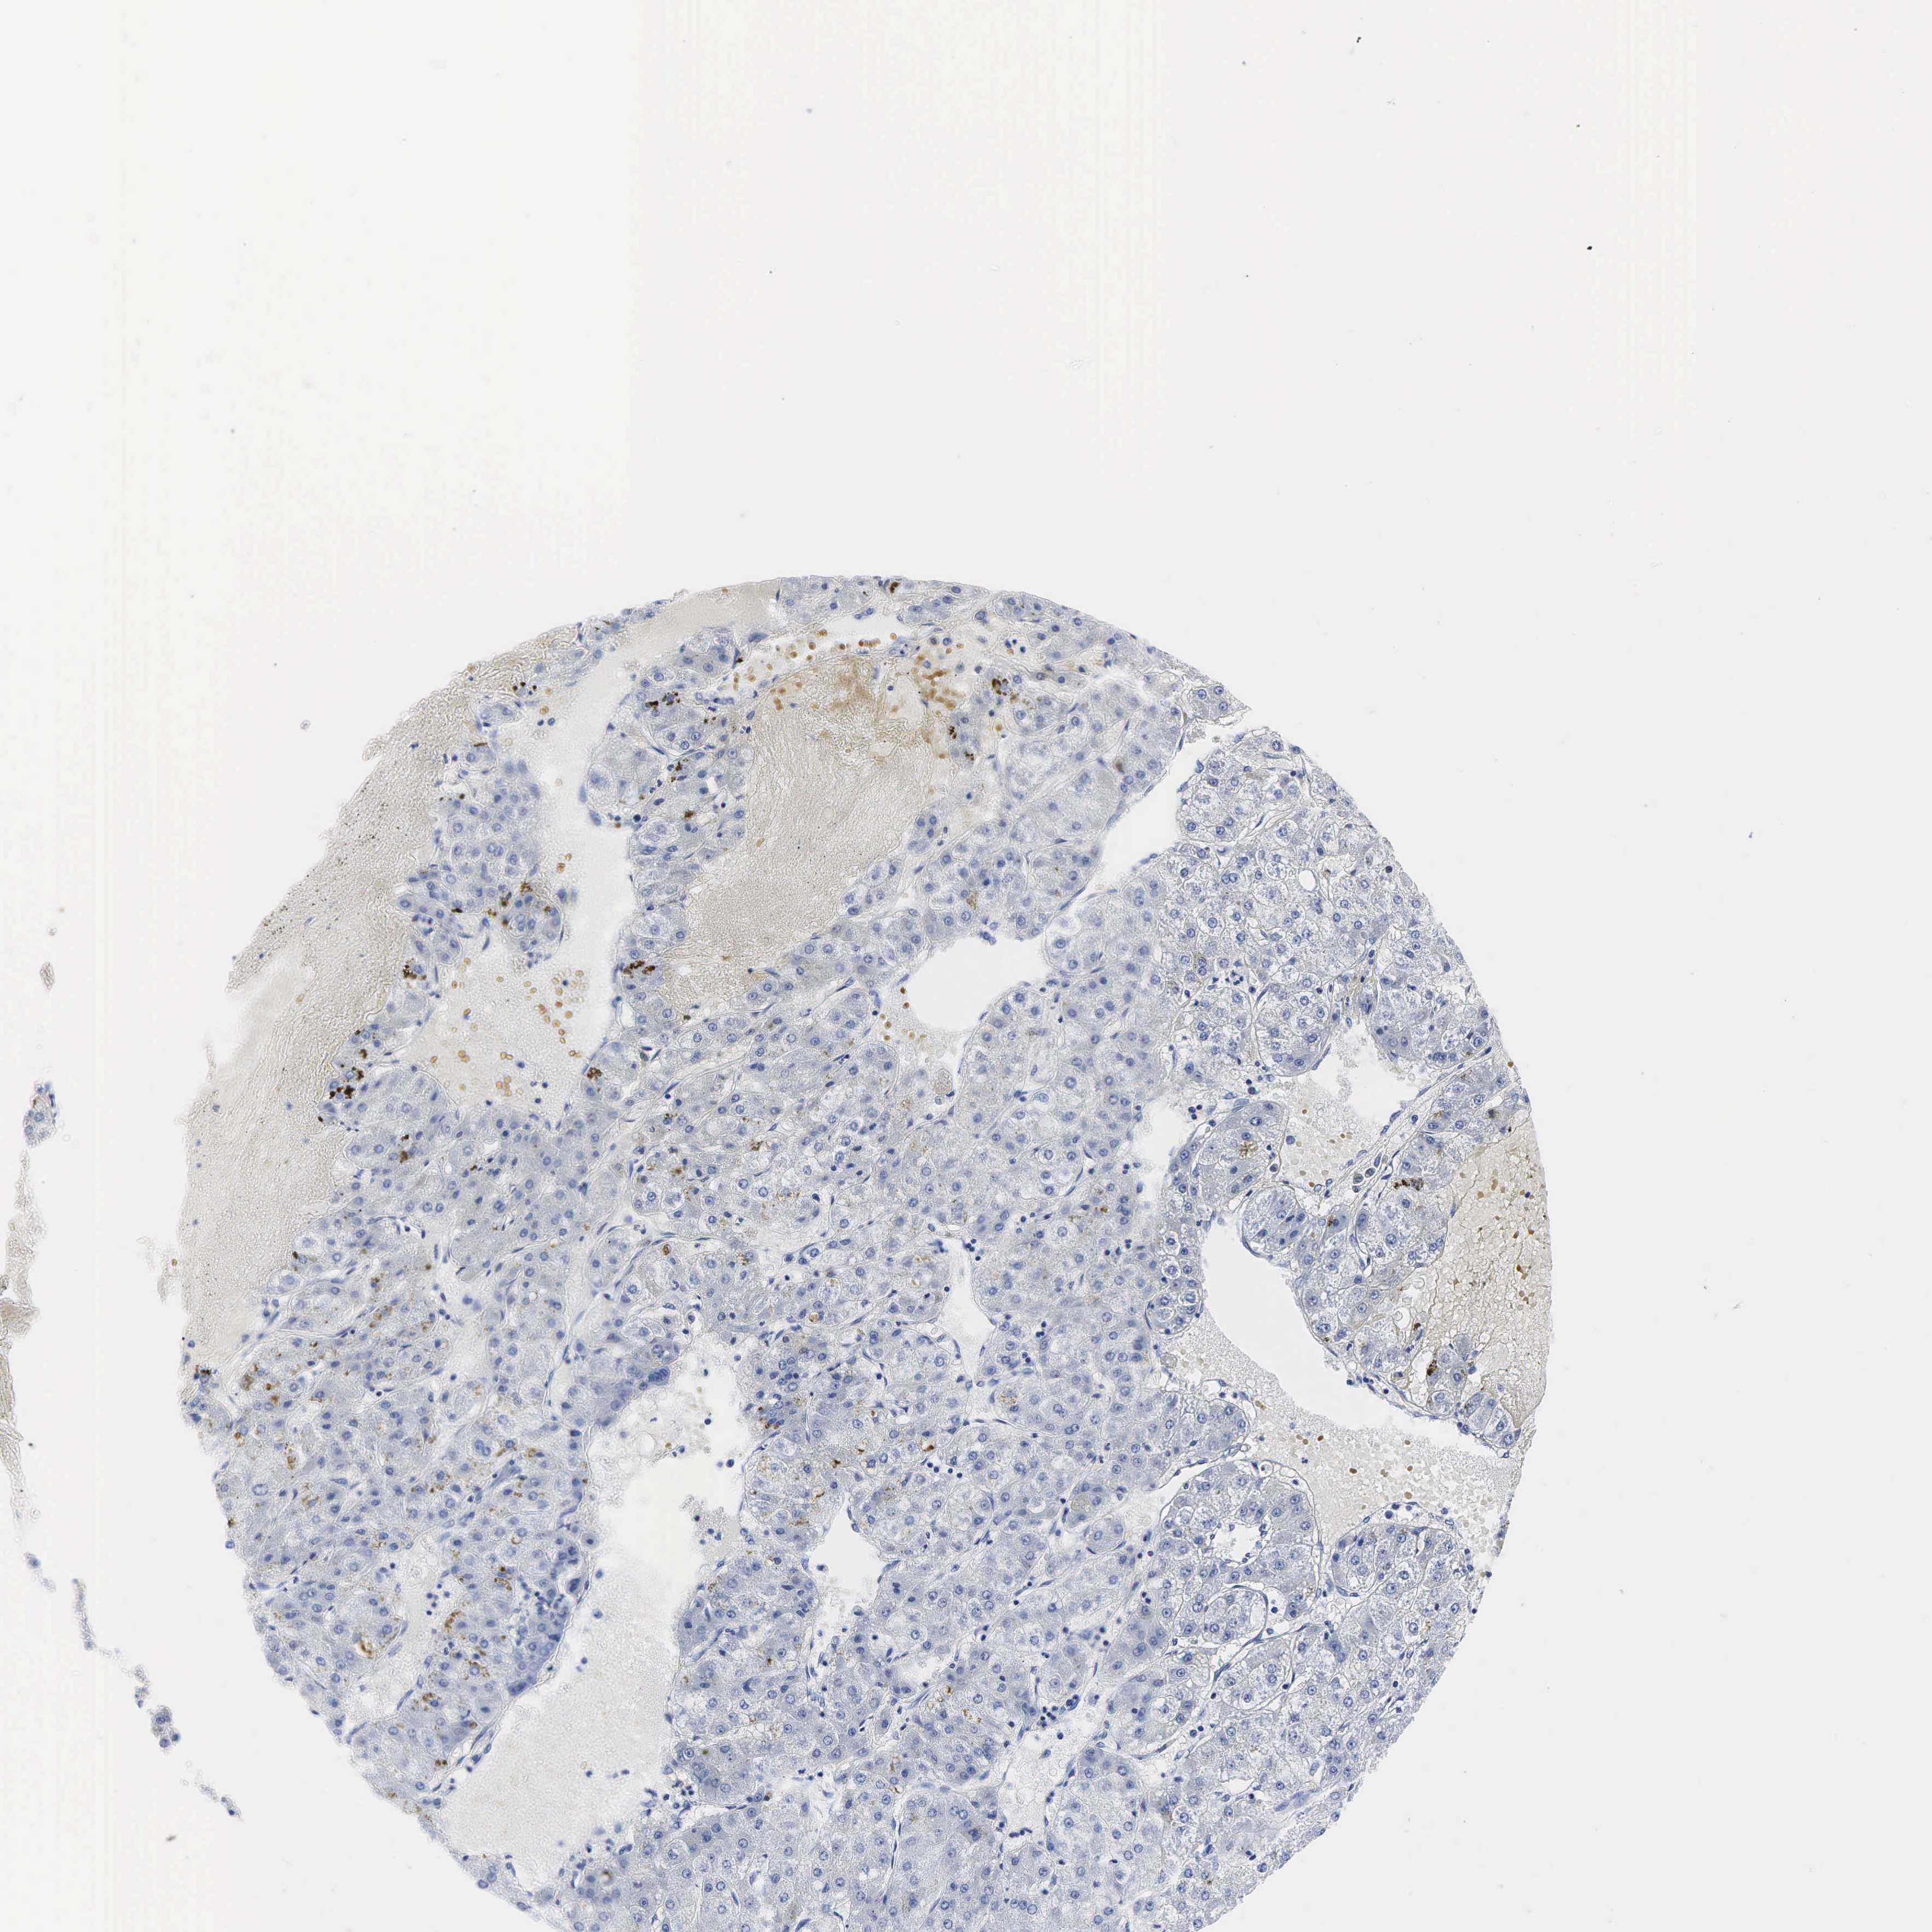

LIVER CANCER - Protein expressioni

A mouse-over function shows sample information and annotation data. Click on an image to view it in a full screen mode. Samples can be filtered based on level of antibody staining by selecting one or several of the following categories: high, medium, low and not detected. The assay and annotation is described here.

Note that samples used for immunohistochemistry by the Human Protein Atlas do not correspond to samples in the TCGA dataset.

Antibody stainingi

Antibody staining in the annotated cell types in the current human tissue is reported as not detected, low, medium, or high, based on conventional immunohistochemistry profiling in selected tissues. This score is based on the combination of the staining intensity and fraction of stained cells.

Each image is clickable and will lead to virtual microscopy that enables deeper exploration of all samples and also displays staining intensity scores, fraction scores and subcellular localization as well as patient and tissue information for each sample.

Antibody HPA002740

Antibody CAB000077

Antibody CAB056155

Staining

High

Medium

Low

Not detected

Intensity

Strong

Moderate

Weak

Negative

Quantity

>75%

75%-25%

<25%

None

Location

Nuclear

Cytoplasmic/membranous

Cytoplasmic/membranous,nuclear

Carcinoma, Hepatocellular, NOS

Cholangiocarcinoma

Carcinoma, metastatic, NOS